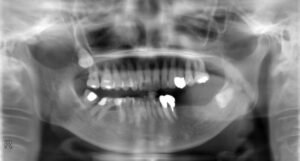

下顎大臼歯1本欠損症例

BEFORE AFTER 34歳男性/下1本欠損/インプラント埋込手術 【治療内容】 右下第一大臼歯の被せ物が取れて来院…